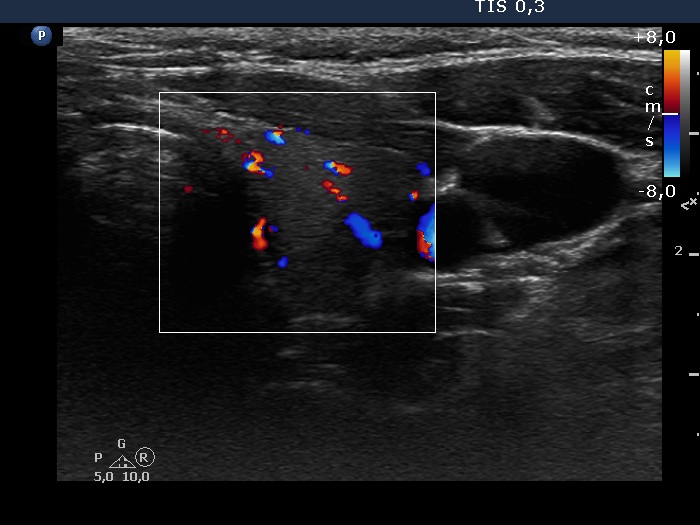

Consecutive patients with the final diagnosis of Hashimoto's thyroiditis - case 36 (574) (ultrasonographic picture 6)

Left lobe, transverse view, color Doppler mode. The vascularization is a bit increased.